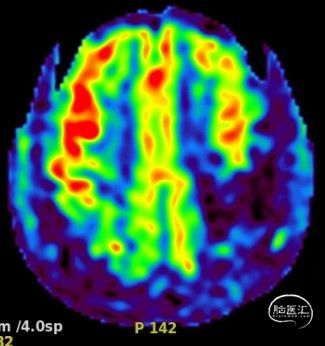

磁共振ASL灌注:两侧大脑半球CBF无明显差别: